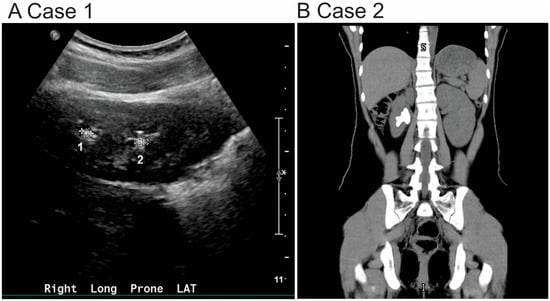

In the renal clinic, her serum creatinine and kidney function were within normal limits. However, 24 h urine studies showed hypercalciuria and hypocitraturia. Potassium citrate therapy was initiated along with recommendations for increased oral fluid intake and dietary sodium restriction. Despite these measures, the patient continued to experience symptoms and underwent two surgical interventions for left ureterolithiasis and left ureteral calculi. Follow-up renal ultrasound showed persistent non-obstructing renal stones measuring 3–4 mm (Figure 1A).

She was subsequently evaluated in urology after being discharged from the ED. A repeat non-contrast CT imaging of the abdomen and pelvis revealed a 3.5 cm staghorn calculus occupying the mid to lower pole of the right kidney, extending into the renal pelvis (Figure 1B). Her basic metabolic panel and other laboratory studies were within normal limits. Stone analysis determined 100% cystine composition. She was referred to nephrology for further evaluation.

Figure 1. Radiographic findings in two pediatric patients diagnosed with cystinuria. (A) Renal ultrasound of Case 1: The kidneys are normal in size and position. In the right kidney, there are subcentimeter calculi at the upper and lower poles, each measuring up to 4 mm (indicated as 1 and 2). In the left kidney, a 3 mm nonobstructing calculus is seen at the lower pole (data not shown). No hydronephrosis or hydroureter is present. (B) Non-contrast CT of the abdomen and pelvis (Case 2): A 3.5 cm staghorn calculus is seen extending from the mid to lower pole of the right kidney into the renal pelvis. No ureteral or left-sided calculi are identified.

Imaging plays a crucial role in diagnosis and follow-up. CT scans are highly sensitive and provide detailed assessment in these cases, particularly for complex stones like staghorn calculi. Renal ultrasound remains the first-line imaging modality in children due to its safety and absence of ionizing radiation [14].